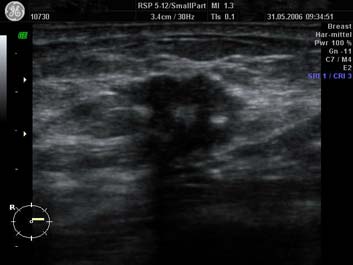

Eine zusätzliche, sinnvolle Ergänzung zur Früherkennung von Brustkrebs und anderen gutartigen Tumoren können Sie mit der Durchführung einer hochauflösenden Ultraschalluntersuchung der Brustdrüsen erreichen. Ein großer Vorteil der Sonografie, besteht darin, dass diese Untersuchung völlig frei von Nebenwirkungen ist und somit auch beliebig oft wiederholt werden kann.

Bei jüngeren Frauen, bei denen wegen des besonders dichten Drüsenkörpers noch keine Mammografie empfohlen wird, ist die Ultraschalluntersuchung der Röntgenuntersuchung meistens überlegen. Die gilt auch für ältere Frauen unter einer Hormonbehandlung, da auch hier die Dichte der Drüsenkörpers wieder zunimmt.

Das Erkennen von Tumoren der Brust durch die Sonographie setzt einerseits Kompetenz und Erfahrung des Untersuchers, sowie Ultraschallgeräte neuester Gerätegeneration  voraus. Es sind dies High-End-Geräte, die weit über den Standard der entsprechenden Organuntersuchung hinausgehen. Wir bieten ein Hochleistungsultraschall (bis 14 MHZ mit 3 D Technik) im Rahmen der Brustkrebsdiagnostik an. Mit Erhöhung der Frequenz verbessert sich die Auflösung des Ultraschall- Bildes und die Detailgenauigkeit erheblich.

Darüber hinaus hat sich in bestimmten Situationen und bei schwer beurteilbahren Befunden der Einsatz der 3D Ultraschalltechnik etabliert. Somit konnten in der Praxis im Einzelnen schon sehr kleine Krebsgeschwülste im „Coronarschnitt“ dargestellt werden, die weder mammografisch noch mit der normalen Ultraschalltechnik erkennbar waren.

Mamasonografie